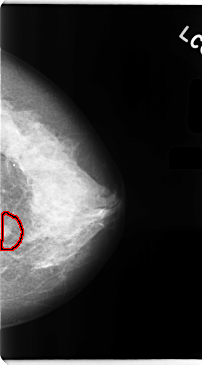

C_0104_1.LEFT_MLO

LEFT_MLO LINES 4680 PIXELS_PER_LINE 2576 BITS_PER_PIXEL 12 RESOLUTION 50 OVERLAY

FILE: C_0104_1.LEFT_MLO.OVERLAY

TOTAL_ABNORMALITIES 1

ABNORMALITY 1

LESION_TYPE MASS SHAPE IRREGULAR MARGINS MICROLOBULATED

ASSESSMENT 5

SUBTLETY 5

PATHOLOGY MALIGNANT

TOTAL_OUTLINES 1

BOUNDARY